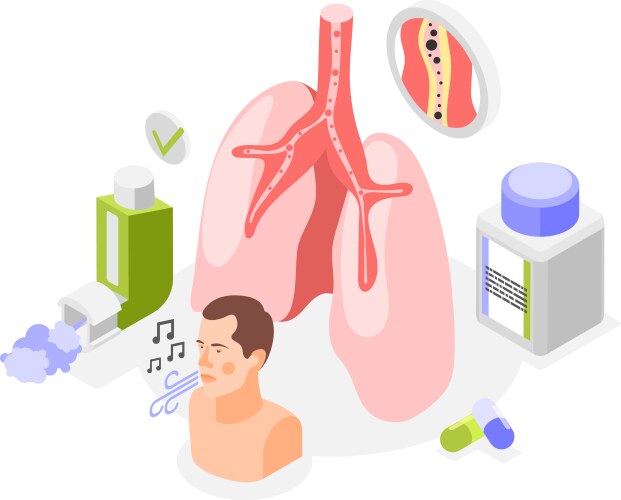

- Asthma

- Medication

- Treatment

- Lung

- Respiratory